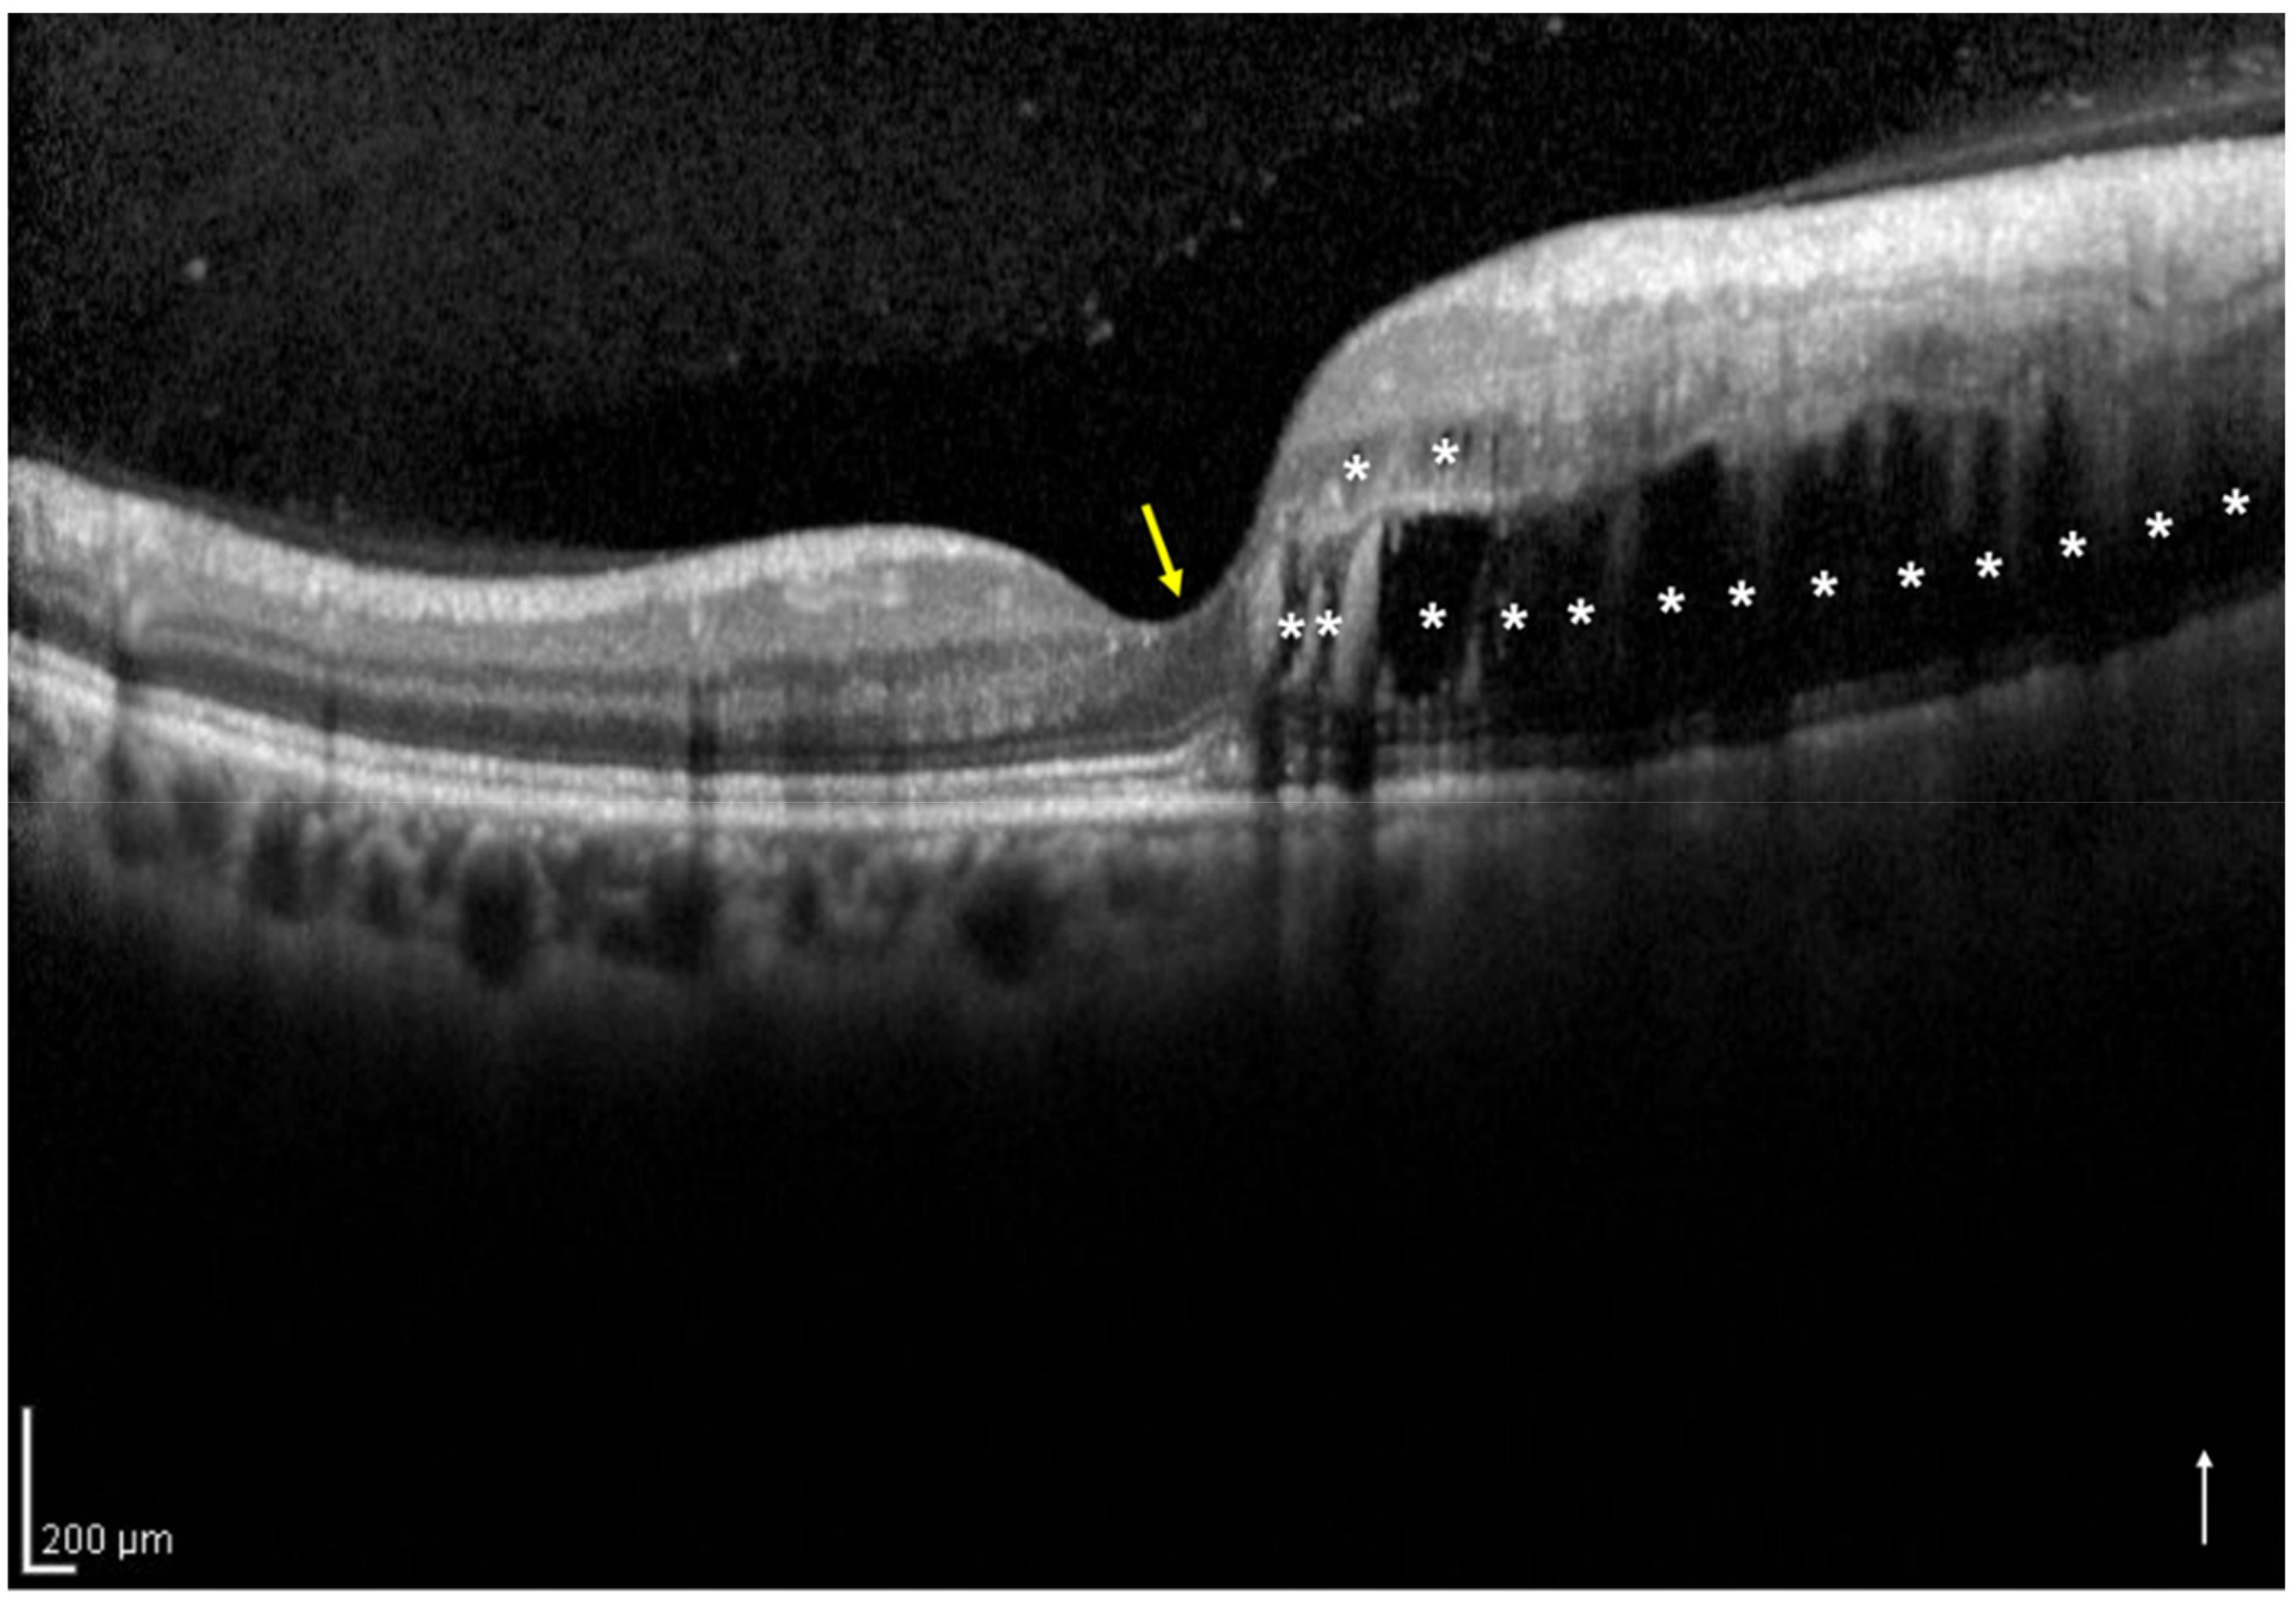

Based on the vertical OCT B-scan image through the fovea at the initial visit, we classified the eyes into two groups: the one-side IRF group included eyes with IRF not involving the central foveola (Figure 1), and the both-sides IRF group included eyes with IRF involving the central foveola (Figure 2). If the vertical OCT B-scan detected subretinal fluid (SRF) involving the central foveola with the IRF not involving the central foveola, the eyes were classified into the one-side IRF group in the present study. Two retinal specialists (H.S. and H.I.) independently classified the eyes included in the two groups and were masked to the BCVA at the initial and 12 months visits and other patient information related to the eyes; a senior observer (M.Z.), who was also blinded to the patient data, made the final decision concerning the classification in case of disagreement.

Figure 1.

A vertical optical coherence tomography (OCT) image of the right eye with intraretinal fluid (IRF) not involving the central foveola secondary to branch retinal vein occlusion of a 54-year-old woman. The OCT shows IRF (asterisks) not involving the central foveola (yellow arrow). The white arrow indicates the OCT scan direction. This eye was classified into the one-side IRF group.